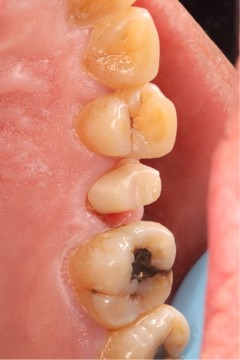

June 20, 2025: The patient's chief complaint is that endodontic treatment was performed on the right maxillary posterior tooth abroad, and a deep carious lesion has been recently detected, requiring restoration. The following are the intraoral photographs taken upon the patient's first visit: a large carious lesion is visible on the occlusal surface of tooth 15 (FDI numbering), with only the buccal wall remaining. Percussion test and cold-hot stimulation test showed no response, and yellow obturation material is visible at the root canal orifices.

July 5, 2025: Completion of root canal retreatment obturation